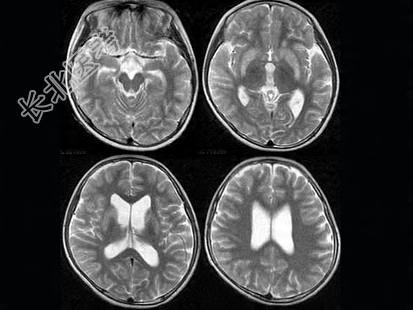

- 单项选择题女,12岁, 进行性肢体震颤1年余,多次出现发音困难, CT、MRI检查如图所示,最可能的诊断为  (    )

A、肝豆状核变性

B、脑萎缩

C、双侧基底节区多发梗死

D、脱髓鞘改变

E、脑积水